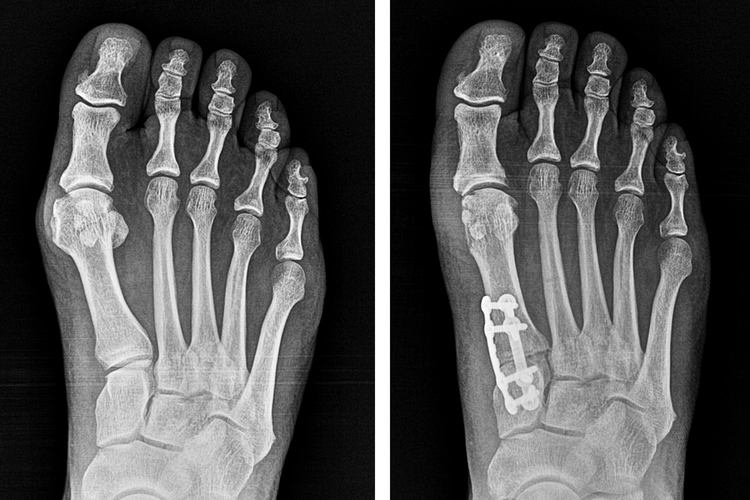

What Is Lapiplasty® 3D Bunion Correction®? All About The Lapiplasty

From bunionectomy.arthrex.com

From www.lapiplasty.com